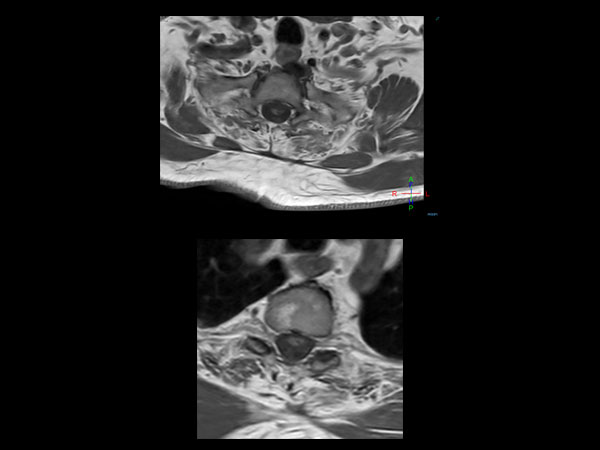

51 year-old man with poor general health and neurological disturbances. Histological examination of the surgical specimen led to the diagnosis of lipomatous ependynoma. Post surgery MRI (resected ependynoma) performed with dS HeadNeck coil with coverage till T4.